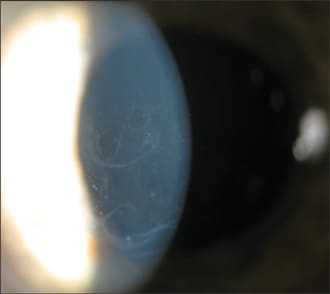

Band keratopathy is a calcium plaque that builds in the anterior corneal surface located in the palpebral fissure zone. (See figure 4.) It usually has a Swiss cheese appearance and often results secondary to chronic uveitis, severe glaucoma or ocular trauma.

Figure 4: Notice the calcium plaque in this patient who has band keratopathy.